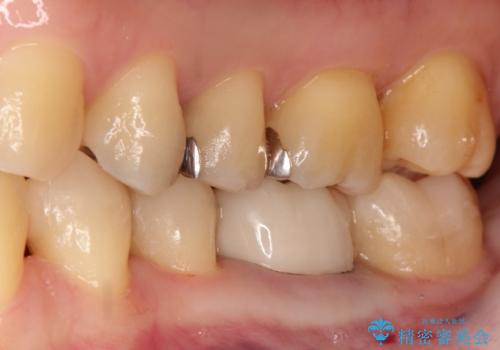

【メタルフリー】白い歯を手に入れたい

- 金属を外して白い歯を手に入れたいとのことで来院されました。

まとめて治療することで通院回数を減らすことができ、見た目も大変満足していただきました。

- 49万円費用は治療当時の料金となります